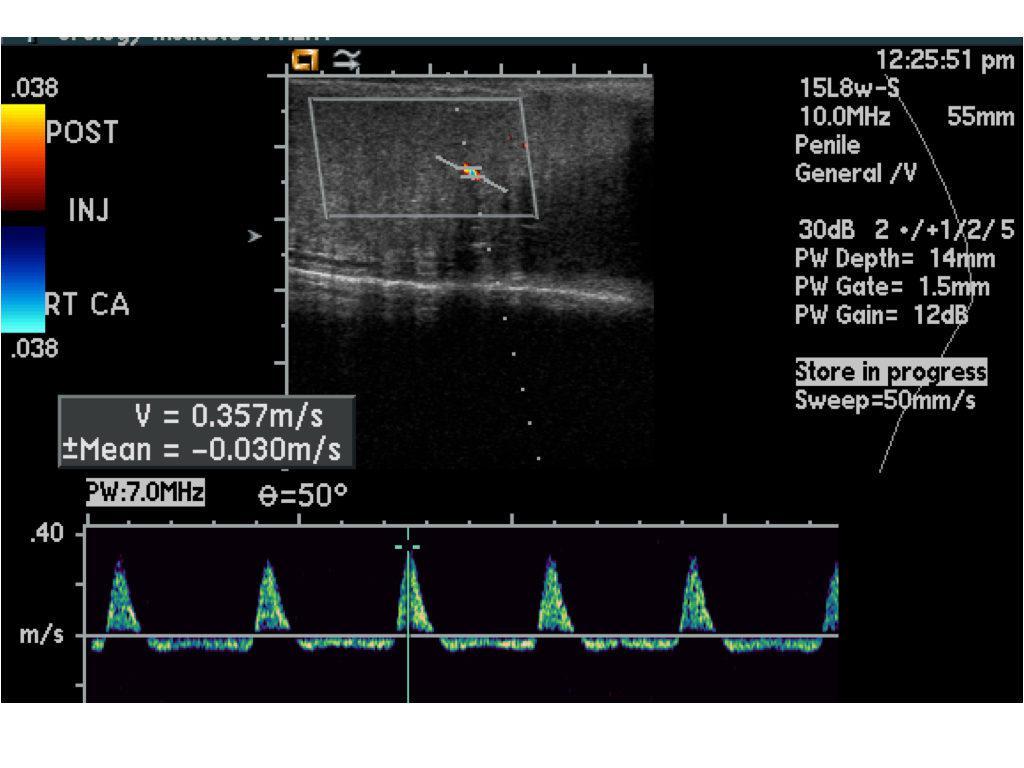

Ereksiyon sebeplerinden en sık görülenleri az önce bahsettiğimiz damarsal yapılardaki problemlerdir. Penise kan taşıyan ataradamar hızlarında ve debilerinde azalma (kalp ve damar hastalıkları, hipertansiyon, diabet vb.) atardamar yetmezliğine yol açar. Atardamar hızları ve debisi normal olduğu halde topladamarların normalden fazla kanı kalbe doğru götürmesi toplardamar yetmezliğne (venöz kaçak) yol açacaktır. Penil doppler ultrason incelemesi ile atardamar ve toplardamarlardaki olası problemler saptanır ve elde edilen bu sonuca uygun tedavi alternatifleri uygulanır. Dolayısıyla sertleşme sorunlarının tedavisi öncesinde deneyimli ellerde ve uygun koşullarda penil doppler ultrason incelemesinin yapılması ve tedavinin buna göre şekillendirilmesi doğru yaklaşımdır.

Penil doppler ultrason incelemsei yaklaşık 30 dk süren bir testtir. Öncelikle ultrason ile penis yapıları ve damarlar değerlendirilir. Daha sonra ereksiyon sağlayıcı ilaçların olduğu bir enjeksiyon yapılır. Bu enjeksiyon ağrılı bir işlem değildir. Daha sonra bir süre beklendikten sonra 5’er dakika aralıklarla atardamar ve toplardamar hızları ve debileri ölçülür. 20.dakika ölçümüde yapıldıktan sonra işlem sonlandırılır. Bütün işlem parametrelerinin olduğu ayrıntılı bir rapor yazılır ve üroloji uzmanının doğru tedavi yöntemini tercih etmesini yolu sağlanır. Bu testte önemli olan hastanın sakin, kalabalık olmayan, gürültünün olmadığı bir ortamda bu işlemi yapmak ve bu test için yeterli zamanı ayırmaktır. Hastane ortamlarındaki kalabalık ve gürültülü alanlarda bu testi yapmak doğru sonuçların alınmamasına yol açacaktır.